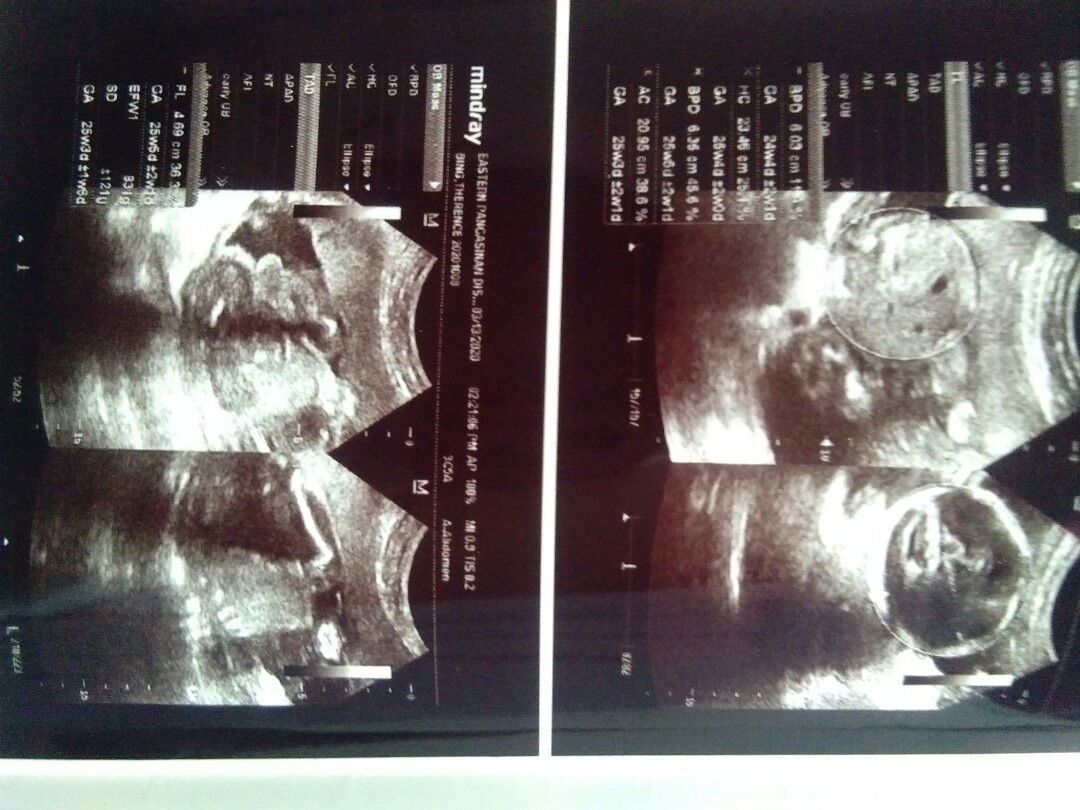

BAse sa picTures mga Momsh . anOng gender ni baby nakikita nYo? 25weeks uLtrasound po yan

Ask ko lang mga sis may posibilidad pO ba na magbagO gender ni baby ? kase nagpauLtrasound akO nun 25weeks ako BabyBoy . nakabile naKo mga gamit baka mmya nyan baby girl pla . may ganun ba ? asap